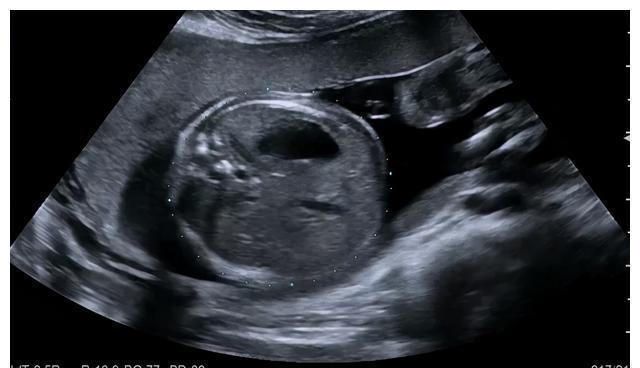

(5)胎儿心脏:显示并观察胎儿心脏四腔心切面、左心室流出道切面、右心室流出道切面、三血管气管切面。怀疑胎儿心脏大血管畸形者,建议进行针对性产前超声检查(胎儿超声心动图检查);

(4)胎儿胸部:观察胎儿双肺、心脏位置;